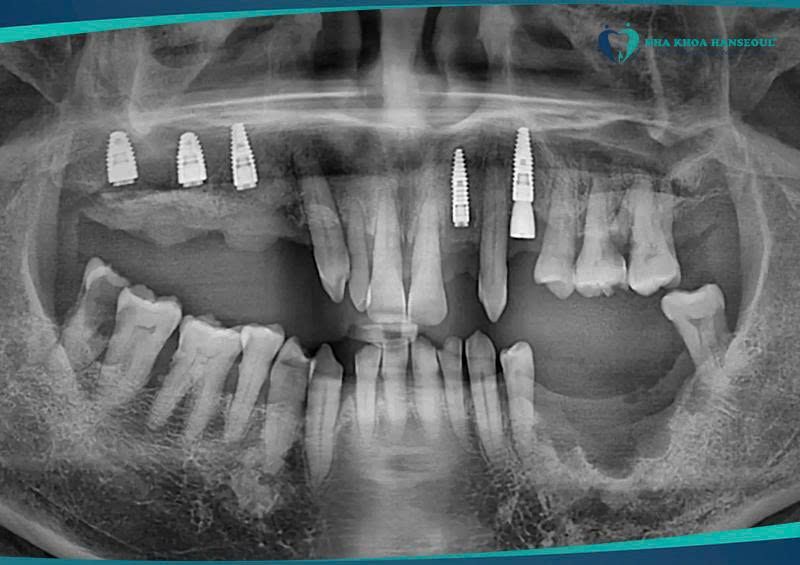

Đến khi thấy việc ăn uống ảnh hưởng quá nhiều đến sinh hoạt hằng ngày, chú quyết định tìm đến Nha khoa Hanseoul để kiểm tra và tư vấn bác sĩ. Kết quả thăm khám cho thấy xương ở một số vị trí đã tiêu nhiều do mất răng lâu, đặc biệt ba răng hàm trên (14 – 16 – 17) cần ghép bột xương và đặt màng xương để tái tạo nền vững. Phác đồ điều trị được thạc sĩ, bác sĩ Trần Việt Hà đưa ra gồm: cấy 5 trụ implant và phục hình 6 răng (bắc cầu răng 36 trên trụ răng 35 và 37) — kế hoạch rõ ràng, bài bản và phù hợp nhất để chú có thể ăn uống bình thường trở lại.

Với sự tư vấn của bác sĩ Hà, chú Tuấn Ngọc đã lựa chọn loại trụ implant tốt nhất thế giới - dòng Straumann của Thuỵ Sỹ để phục hình răng. Đây là loại trụ có khả năng tích hợp xương vô cùng tốt, rất phù hợp cho những người bị tiêu xương nhiều, mất răng lâu năm, có bệnh lý nền. Và trụ Straumann được bảo hành trọn đời, do vậy khách hàng có thể an tâm hoàn toàn.

Để đảm bảo tích hợp xương tốt và quá trình lành thương được tối ưu, hành trình điều trị của chú được chia làm hai lần: lần đầu cấy implant và ghép xương cho ba răng hàm trên; lần hai cấy thêm implant 35 – 37 và phục hình cầu sứ qua vị trí 36 để hoàn thiện khớp cắn. Tất cả các bước đều được theo dõi sát sao, từng chi tiết nhỏ đều được bác sĩ kiểm soát để chú cảm thấy yên tâm nhất.